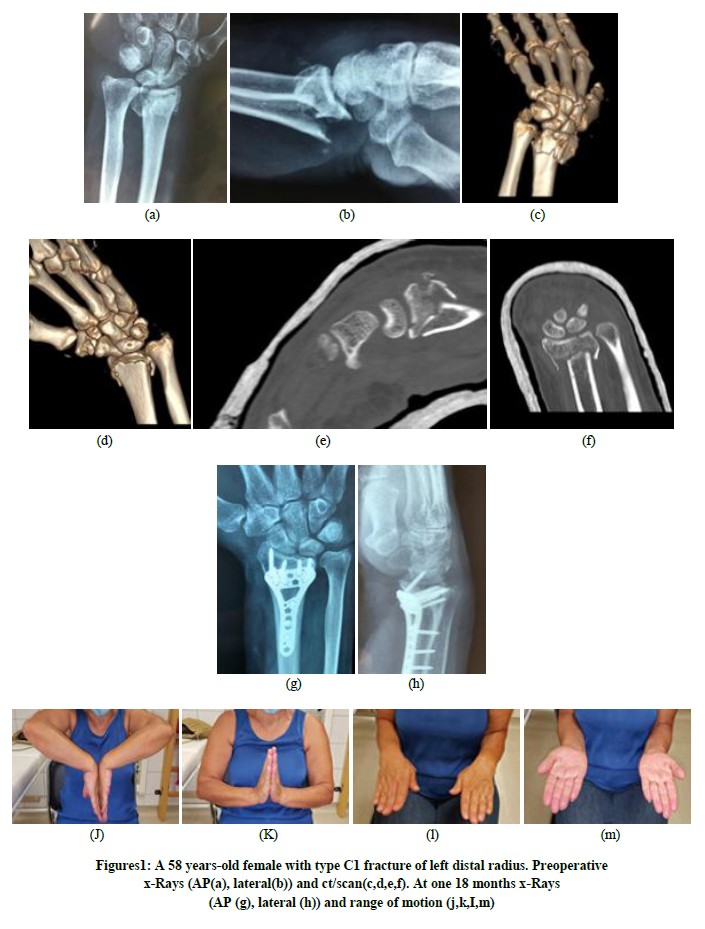

Volar Locking Plate for Distal Radius Fractures: Functional Outcomes and Complication Rates with a Minimum of One Year Follow-Up

Kastanis G, Pantouvaki A, Kapsetakis P, Spyrantis M, Magarakis G, Christoforidis C, Stavrakakis I

International Journal of Innovative Research in Medical Science·May 28, 2021